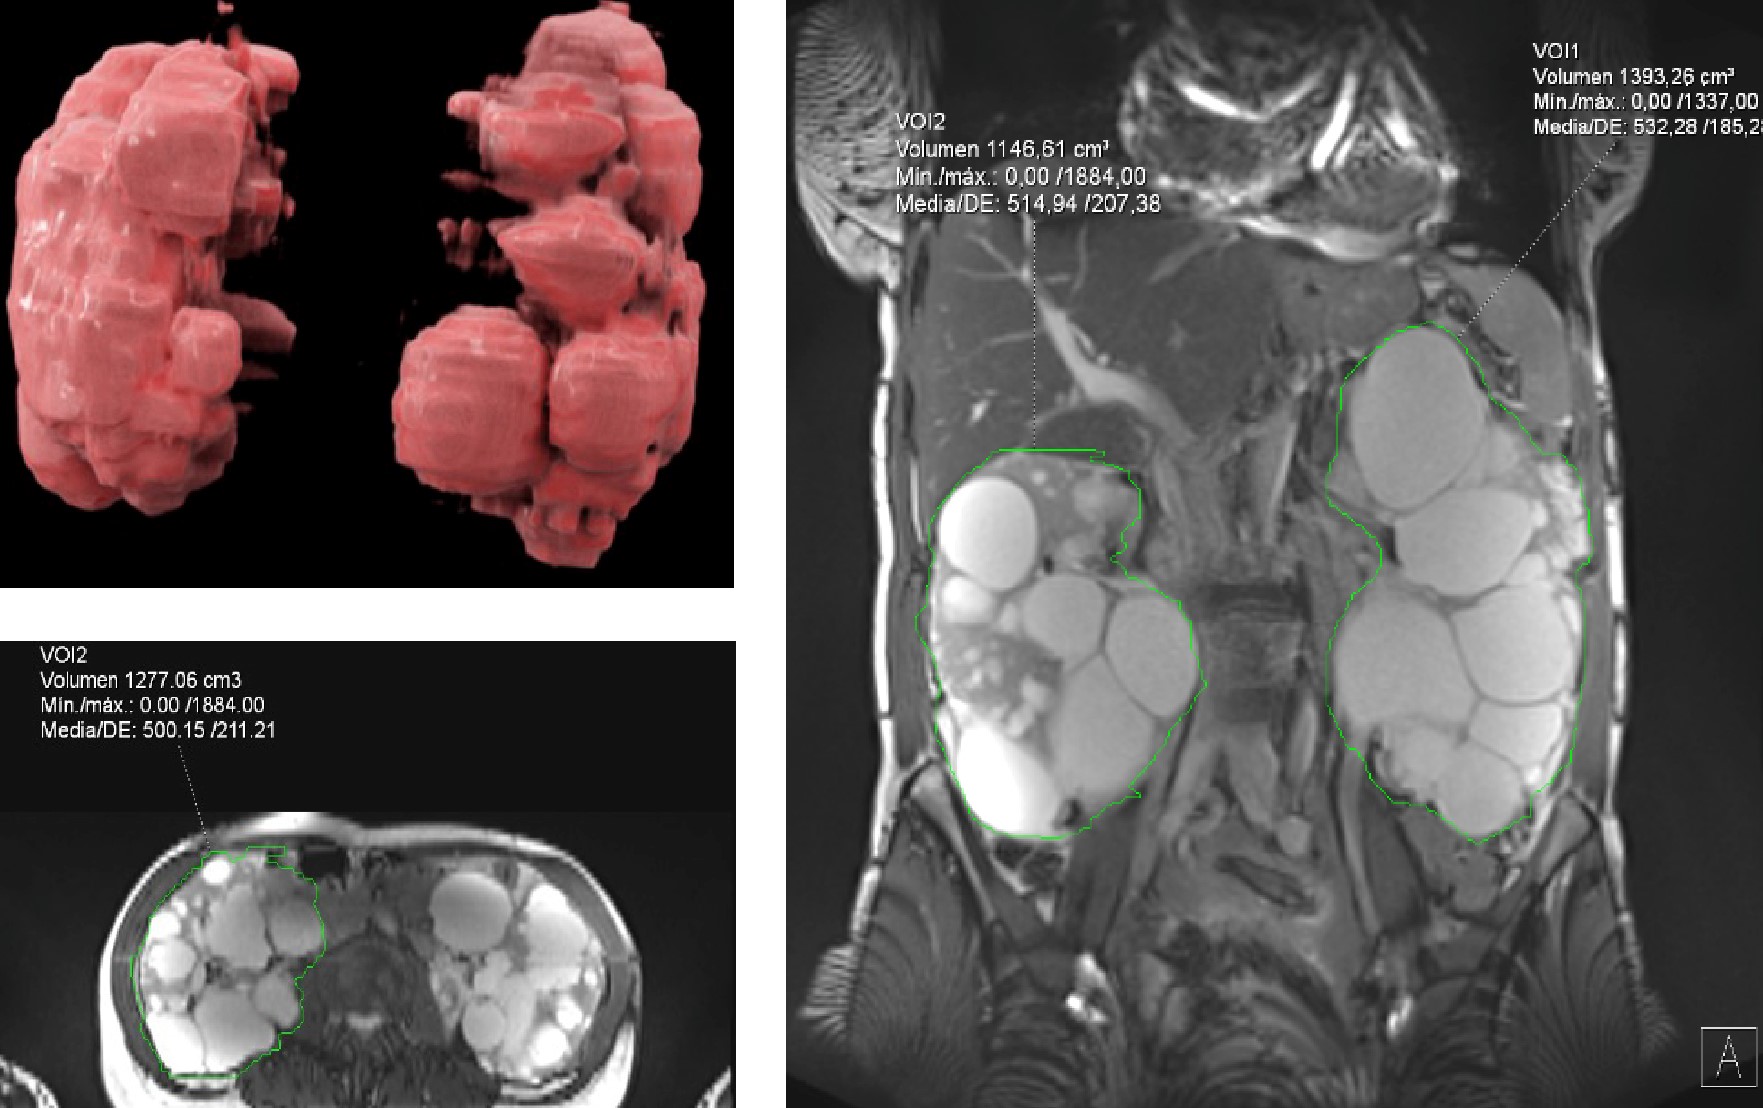

Cálculo mediante segmentación de volumetría renal a través de resonancia magnética con reconstrucción volumétrica 3D en paciente con poliquistosis renal bilateral

La resonancia magnética de 3 teslas con la que cuenta Resona, utilizando la segmentación renal a través de inteligencia artificial y planimetría, ofrece cálculos del VRT, más precisos, sin irradiación y reproducibles, además de permitir el estudio adicional de la patología renal y la complicación de los quistes, su crecimiento o presencia de hemorragia, así como obtener imágenes 3D.